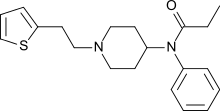

Anilidopiperidines

- 3-Allylfentanyl

- 3-Methylfentanyl

- 3-Methylthiofentanyl

- 4-Phenylfentanyl

- Alfentanil

- α-Methylacetylfentanyl

- α-Methylfentanyl

- α-Methylthiofentanyl

- Benzylfentanyl

- β-hydroxyfentanyl

- β-hydroxythiofentanyl

- β-Methylfentanyl

- Brifentanil

- Butyrfentanyl

- Carfentanil

- Fentanyl

- Lofentanil

- N-Methylcarfentanil

- Mirfentanil

- Ocfentanil

- Ohmefentanyl

- Parafluorofentanyl

- Phenaridine

- R-30490

- Remifentanil

- Sufentanil

- Thenylfentanyl

- Thiofentanyl

- Trefentanil

Structures